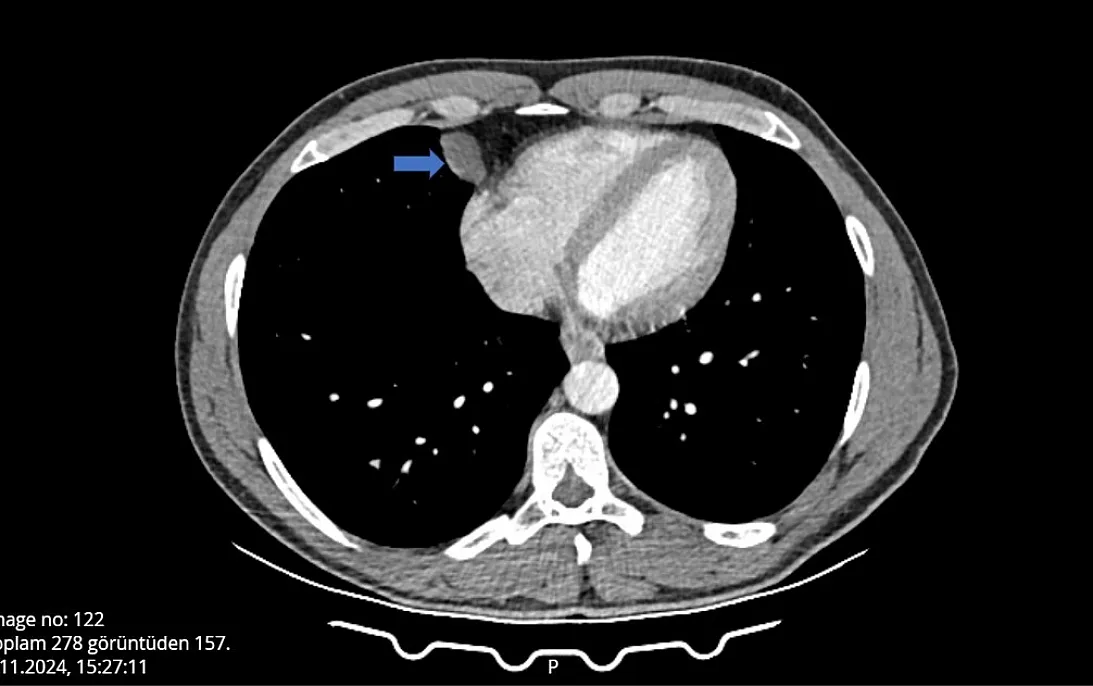

Yaptığı seyahat dönüşü öksürme ve hapşırma krizlerine tutulup grip olduğunu düşünen yat kaptanı hastaneye başvurdu, yapılan kontrolde akciğer ve kalp arasında kist olduğu tespit edildi. Ameliyata alınan kaptan, Video Yardımlı Torakoskopik Cerrahi (VATS) ile 10 dakikalık operasyon sonucu sağlığına kavuştu.

“Uzun bir seyahate çıktım. Seyahat dönüşü soğuk algınlığı gibi bir şey oldu. Omuzumdan bir ağrı başladı ve nefes alırken, öksürürken, hapşırırken nefesim kesiliyordu. Hastane aciline gittim, kist olduğunu söylediler ve burada Eğitim ve Araştırma Hastanesi'ni önerdiler. Kistin ciğerden kalbe sıçramak üzere olduğunu söylediler. Hemen ameliyata alındım ve 1 günde sağlığıma kavuştum. Ben komple göğüs kısmımın açılacağını sanıyordum ve açıkçası korkmuştum. Küçük bir noktadan girildi ve bu kadar hızlı taburcu olacağını düşünmüyordum. Hocalarımdan Allah razı olsun.”